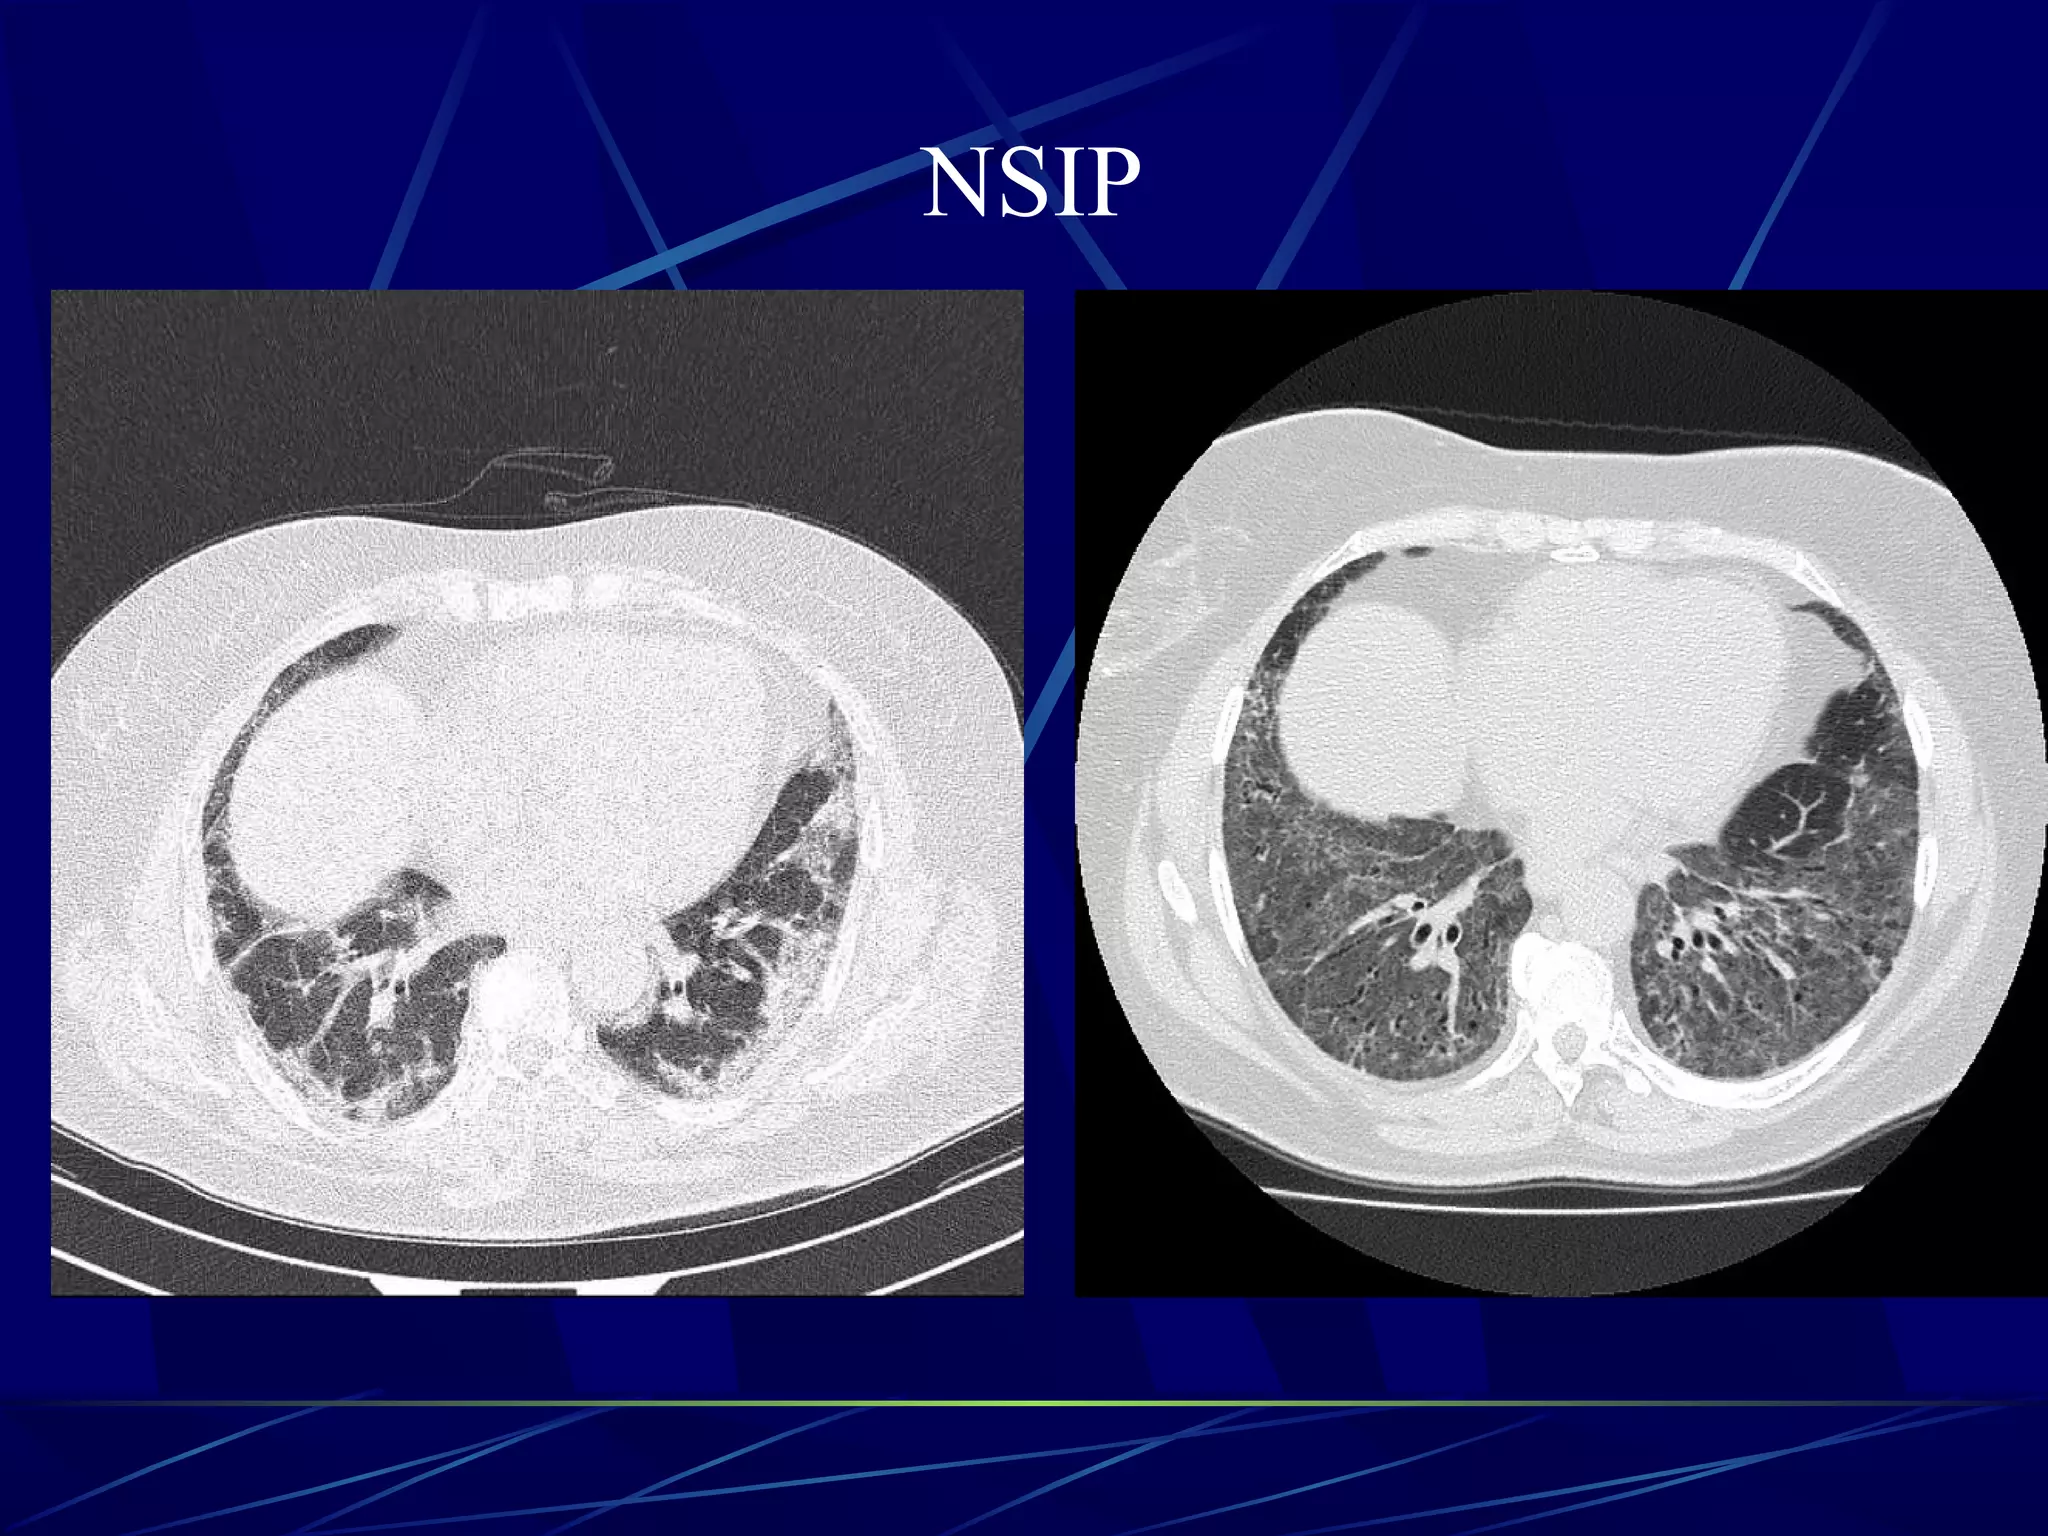

NSIP

Non-specific interstitial pneumonia

-fibrotic non specific interstitial pneumonia: more common

-cellular non specific interstitial pneumonia: less common

Prognosis is much better when compared with UIP with 90% 5 years

survival rate for cellular and 45-90 % 5 years survival in fibrotic subtype.

Common manifestations include:

ground-glass opacities combined with irregular linear or reticular opacities

tends to be a dominant feature: can be symmetrically or diffusely distributed

in all zones or display a basal predominance

there can be relative subpleural sparing 11

- relatively specific sign

reticular opacities (sometimes - minor subpleural reticulation)

irregular linear opacities: with NSIP with fibrosis 6-7

thickening of bronchovascular bundles: with NSIP with fibrosis 6

scattered micronodules

in advanced disease

traction bronchiectasis

consolidation

microcystic honeycombing

Non-specific interstitial pneumonia -fibroticnon specific interstitial pneumonia: more common -cellular non specific interstitial pneumonia: less common Prognosis is much better when compared with UIP with 90% 5 years survival rate for cellular and 45-90 % 5 years survival in fibrotic subtype. Common manifestations include: ground-glass opacities combined with irregular linear or reticular opacities tends to be a dominant feature: can be symmetrically or diffusely distributed in all zones or display a basal predominance there can be relative subpleural sparing 11 - relatively specific sign reticular opacities (sometimes - minor subpleural reticulation) irregular linear opacities: with NSIP with fibrosis 6-7 thickening of bronchovascular bundles: with NSIP with fibrosis 6 scattered micronodules in advanced disease traction bronchiectasis consolidation microcystic honeycombing